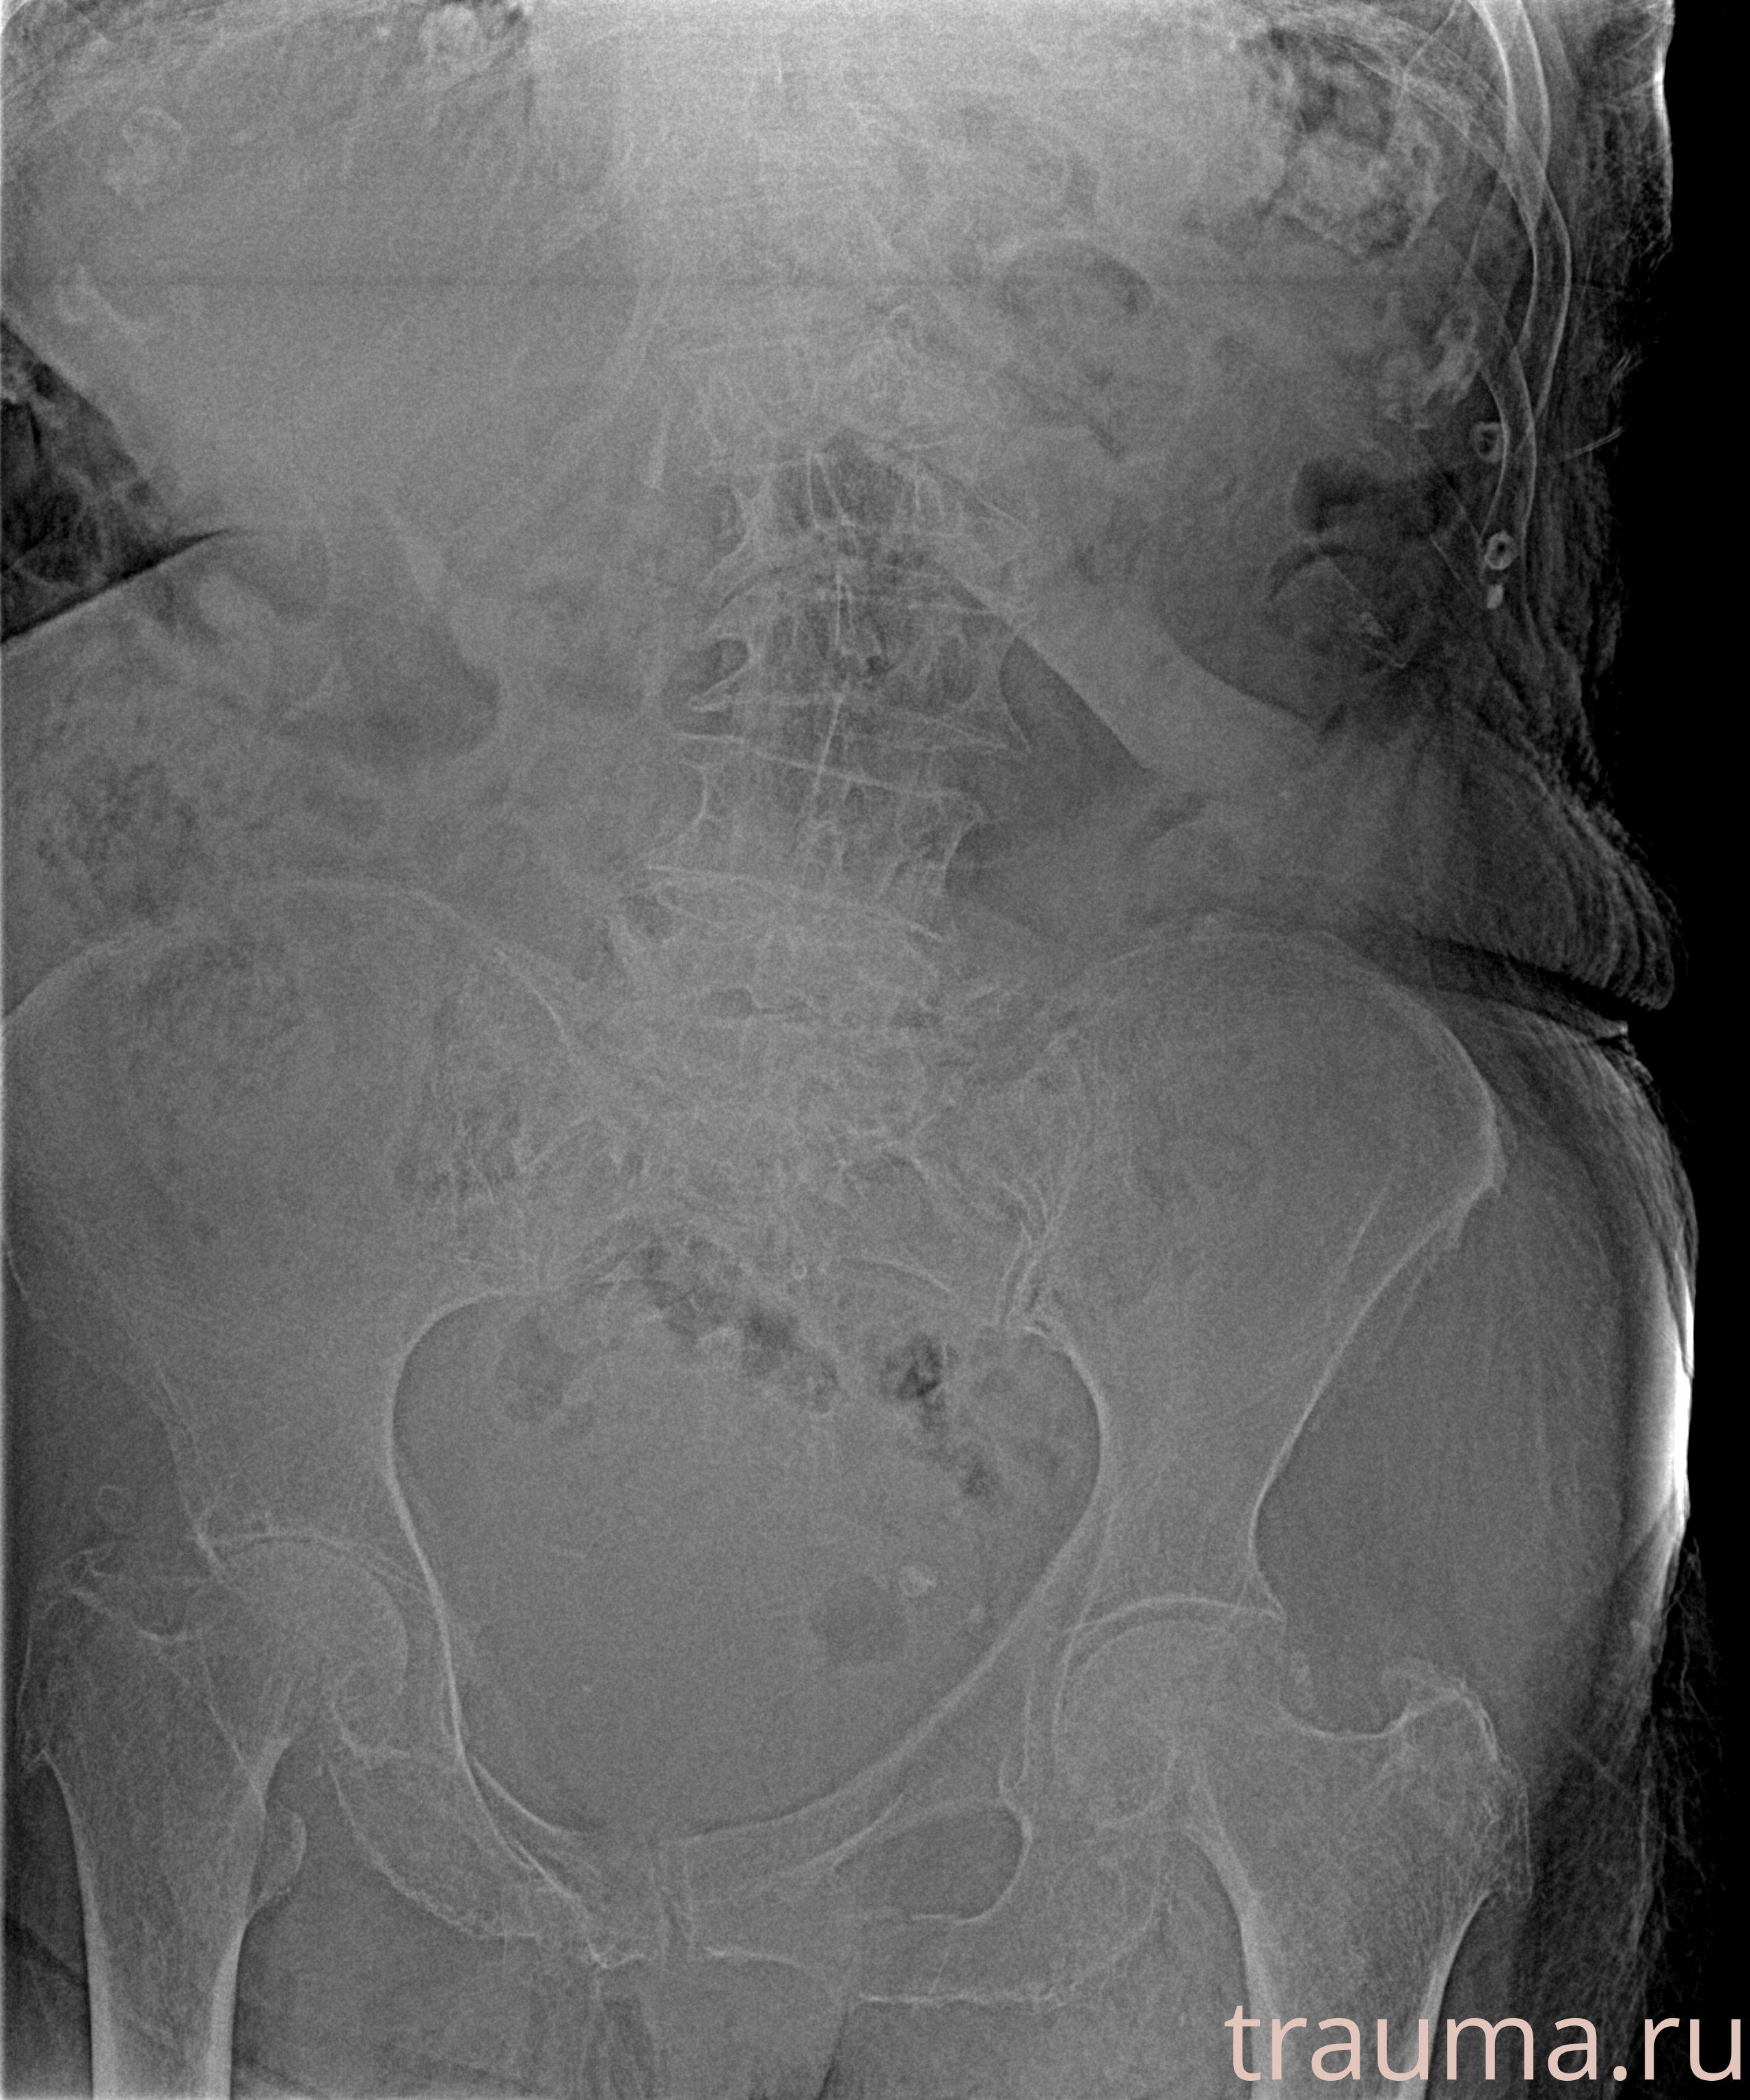

Рентгенограммы

Рентген на дому: по вашему адресу приезжает врач-рентгенолог, травматолог-ортопед с мобильным рентгеновским аппаратом, проводит диагностику травмы или заболевания, делает необходимые рентгенограммы, дает рекомендации по дальнейшему лечению. Получить качественные снимки в домашних условиях возможно благодаря уникальной методике, разработанной МосРентген Центром для института  Склифосовского